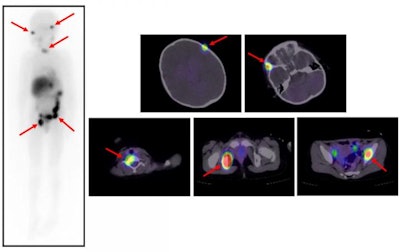

A team from Kanazawa University found that high-dose 131-iodine-metaiodobenzylguanidine (131I-MIBG) treatment could improve prognoses in children with high-risk disease.

Neuroblastoma typically forms in the adrenal glands or the nervous system, and it is the most common cancer in children outside the head, the researchers noted. Children with low- and intermediate-risk disease can be cured by surgery or chemotherapy, but those with high-risk disease undergo aggressive chemotherapy, stem cell transplants, or radiation and often have poor outcomes (Annals of Nuclear Medicine, March 26, 2020).

Kinuya and colleagues evaluated 19 patients with high-risk neuroblastoma who were treated with high-dose 131I-MIBG at Kanazawa University Hospital, analyzing patient outcomes over a five-year period.